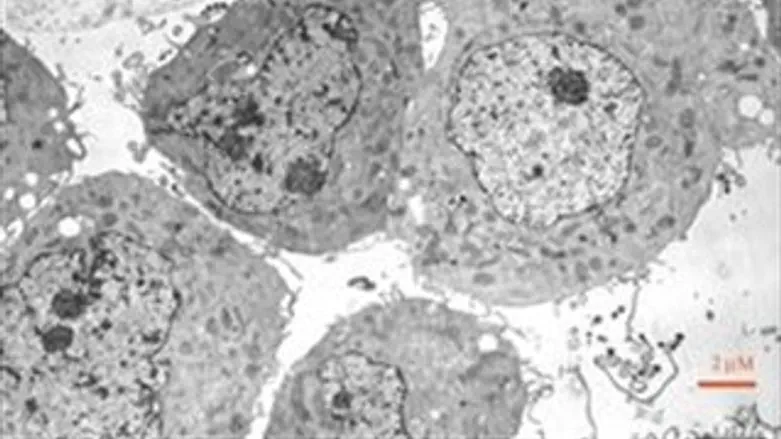

תהליך של היווצרות דלקת בגוף מתרחש כשחיידק (פתוגן) חודר לרקמה בגוף. חלק מהתאים "הלבנים" (ניוטרופילים) מתחילים להיאבק בפולש במטרה להשמיד ולסלק אותו מהרקמה. במצב נורמאלי - בו התאים מצליחים להשמיד את החיידק – הדלקת מסתיימת כאשר הם עוברים מוות תאי מתוכנן. בשלב זה נכנסים לתמונה תאים "לבנים" מסוג אחר (מקרופאגים) שתפקידם לבלוע את התאים המתים ולהחזיר את הרקמה לתפקוד נורמאלי. בעקבות תהליך הבליעה המקרופאגים מקבלים את היכולת להתחיל בשיקום הרקמה הפגועה ובשלב מסוים - שעד כה לא היה ידוע מתי וכיצד הוא מתרחש - הם עוזבים את הרקמה ונודדים לאיברים של מערכת החיסון, דרך מערכת הלימפה, שם הם מתווכים את תהליך ה"חזרה לשגרה" של הגוף ברמה המערכתית.

החוקרים גילו כי למקרופאגים אלה קיים במצב רגיל "סף בליעה" של שבעה תאים - לאחר שהם בולעים שבעה ניוטרופילים הם מקבלים "רישיון" לעזוב את הרקמה. עוד התברר כי תאים אלה רגישים לקצב ההחלמה של הרקמה, כך שכשהרקמה מחלימה בקצב מזורז, תאים אלה מקבלים אישור לעזוב את המקום מוקדם יותר וכאשר הגוף מתקשה בהחלמה הם נותרים ברקמה גם לאחר שבלעו שבעה תאים. עוד התברר כי במקביל לעזיבת הרקמה עוברים המקרופאגים שינויים ברמה המולקולארית המתחייבים מהתפקיד החדש שאותו הם צריכים למלא. החוקרים אף מצאו חומרים ש"מספרים" לתא על קצב ההחלמה של הרקמה והראו שהזרקה של חומרים אלה מזרזת את המעבר של המקרופאגים לאיברי מערכת החיסון ובמקביל מגייסת מקרופאגים חדשים לרקמה הפגועה, שימשיכו את תהליך הריפוי.